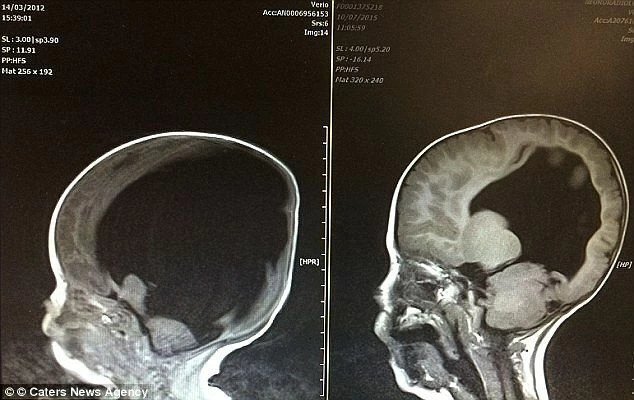

Когда младенец появился на свет, большая часть его головы была заполнена жидкостью. В следствие чего у маленького Ной мозг составлял всего 2% от нормы. Ниже груди все тело ребенка было парализовано. Мальчику сделали срочную операцию по установлению в черепе шунта, а после восстановления мать с ребенком выписали из больницы.

Прогнозы врачей относительно жизни Ноя были самые неутешительные, но родители верили, что есть шанс на счастливый исход. Они окружали своего малыша огромной заботой и любовью, посетили множество клиник. И чудо все-таки произошло. К трем годам наполненность мозга ребенка составила 80%.